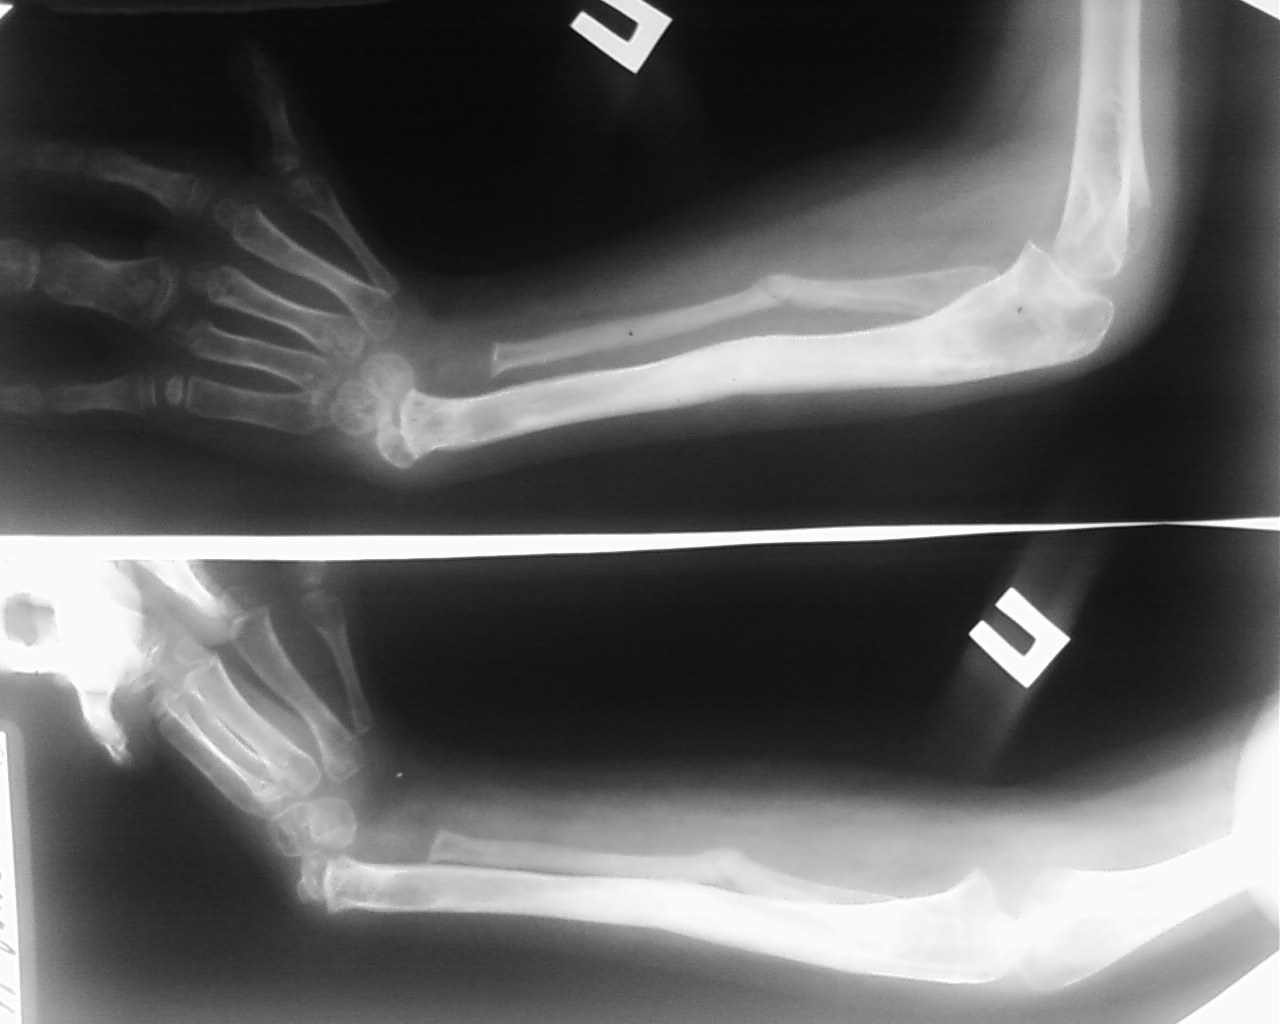

Лучевая косорукость

Ребёнок Д.9 лет, клинический диагноз врожденная правосторонняя лучевая косорукость первой степени.

В мае 2009 года проведено удлинение обеих костей правого предплечья в аппарате Илизарова на 4 см, в процессе дистракции был разрыв регенерата, произведена компрессия в аппарате структура кости восстановлена. Сохраняется порочное положение кисти

В настоящее время наложен аппарат внешней фиксации на правую локтевую кость и третью пястную кость, с целью устранения порочного положения правого кистевого сустава. Уважаемые коллеги, помогите определиться с дальнейшей тактикой лечения данного ребенка. С уважением коллектив ТОО КДКБ г. Ставрополя.